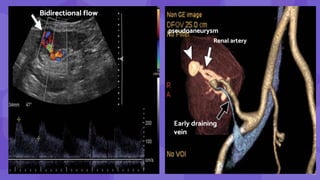

Bidirectional flow

Renal artery

Early draining

vein

pseudoaneurysm

16

15 Bidirectional flow Renal artery Earlydraining vein pseudoaneurysm

• #16 Postbiopsy pseudoaneurysm and arteriovenous fistula (AVF) Color Doppler image shows a round area of bidirectional flow (arrow) in the upper transplant kidney, consistent with a pseudoaneurysm. Spectral analysis at a site of focal aliasing near the pseudoaneurysm shows high-velocity systolic flow and low-resistance diastolic flow, characteristic features of an AVF Three-dimensional volume-rendered image shows the renal artery (white arrow) with an early draining vein (black arrow) as well as the pseudoaneurysm (arrowhead).

• #17 Image from subtraction angiography shows the pseudoaneurysm (arrowhead) and the early draining vein from the AVF (arrow) Same AVF treated with coil embolization. postprocedure AVFs have been reported in up to 10% of renal allograft biopsies, most of which are asymptomatic with no clinically significant hemodynamic consequences. These cases can be treated conservatively and can be followed up with US as needed, with 70% regressing or resolving spontaneously. Large or symptomatic AVFs resulting in abnormal large or persistent gross hematuria or significant hypertension occur in only 1%–2% of cases and can be treated with catheter embolization